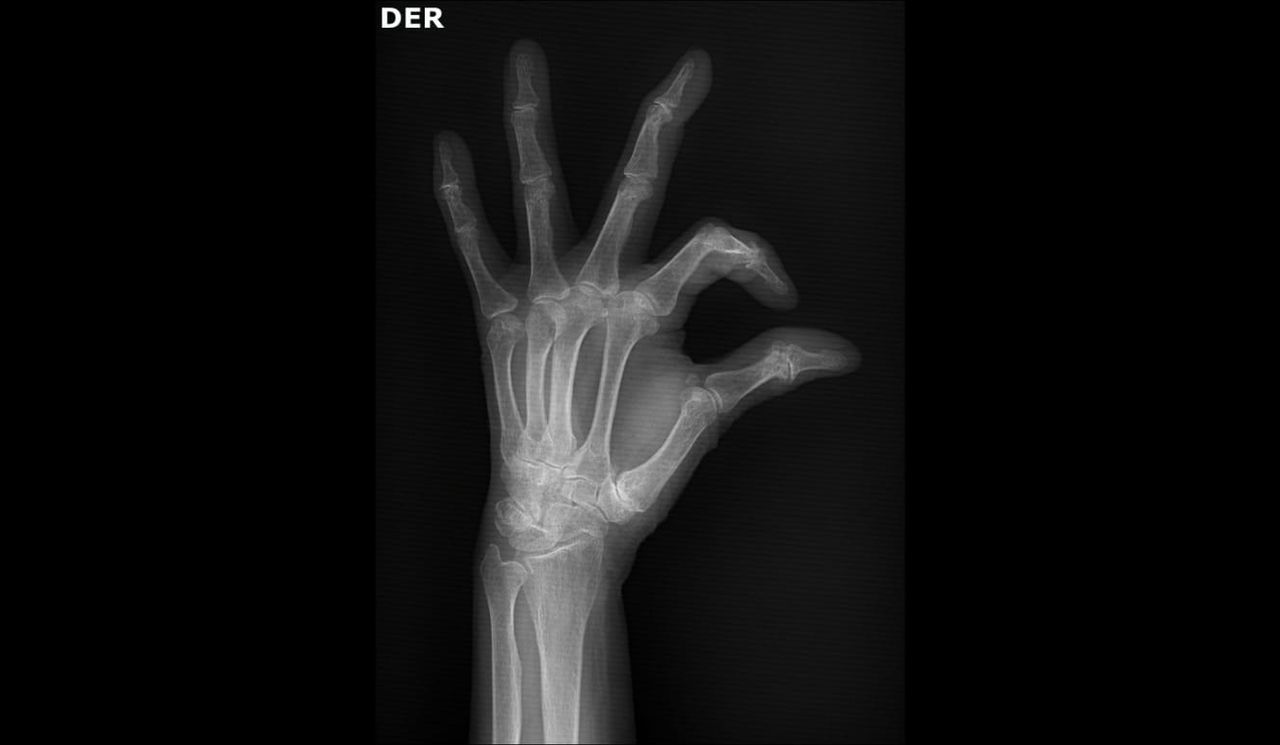

prótesis trapecio metacarpiana como solución tecnológica innovadora para dolor en base de pulgar preservando buena movilidad y función del pulgar